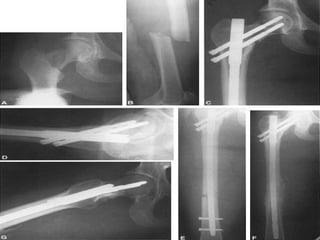

LOCALIZACION Diafisiaria Metafisiaria Epifisiaria Intraarticular Fractura-luxación

RELACION DE LOS FRAGMENTOS ENTRE SI Sin desplazamiento Con desplazamiento: lateral, angulada, rotación, diastasado, cabalgado, impactada

FRAGMENTOS Y SU RELACION CON EL MEDIO EXTERNO Cerrada (abrigada) Abierta

FRACTURA EXPUESTA Es la perdida de continuidad ósea, en  la que el foco de fractura se pone en contacto con el medio ambiente